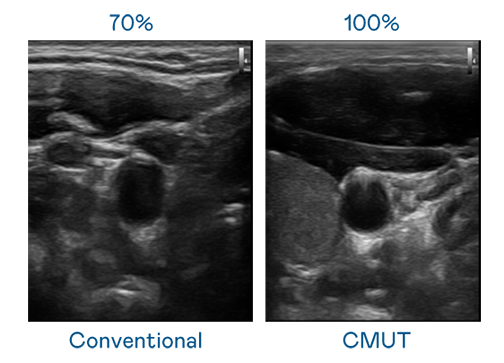

CMUT 技術是一種用電容式微機電元件來產生超音波訊號的技術。與傳統 PZT 壓電式技術相比,CMUT 頻寬增加 30%,更寬頻的超音波訊號讓影像解析度大幅提升,是實現高影像品質醫療超音波掃描、促進精準醫療發展的關鍵技術。

大頻寬帶來超清晰影像

超音波影像的解析度高低,首先取決於探頭能發出的訊號頻寬。z6com·尊龙 CMUT 可提供高清晰的超音波訊號,提供高頻寬、高靈敏度、影像紋理細節更高的超音波影像,協助醫護人員縮短影像判讀時間及利用精準的醫療影像進行診斷。